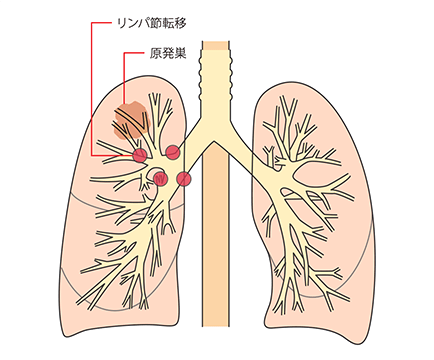

リンパ行性転移は、リンパ液が集まるリンパ節という部位にがんが転移し、そこからリンパ液の流れにのってほかのリンパ節へとがん細胞が広がることです。

肺がんがリンパ節に転移した場合は

人間の体には、血管と同じように全身をめぐるリンパ系というネットワークがあります。リンパ系は、体中に張りめぐらされたリンパ管と、リンパ管の集まるリンパ節からできており、細菌やがん細胞をやっつける免疫機能を担っています。

がんが大きくなって近くのリンパ節に広がると、がん細胞がリンパ管を通って、別のリンパ節へ転移するリンパ行性転移が起こります。肺には多くのリンパ節があるため、肺がんはリンパ行性転移を起こしやすいがんといえます。

リンパ節転移が起こると、リンパ節が腫れて周囲の神経や器官を圧迫するため、いろいろな症状が起こります。

リンパ節への転移とステージ・症状

がんの部位に応じて転移しやすいリンパ節がグループ化されており、それを所属リンパ節といいます。

肺がんでは、肺門(肺の入り口周辺)リンパ節、肺内(肺の中)リンパ節、縦隔(左右の肺に挟まれた空間)リンパ節という3つのグループに分かれます。

所属リンパ節への転移の段階はN因子(NX、N0、N1、N2、N3)で表され、病期(ステージ)を決める要素の一つです。数字が大きくなるほど、転移の範囲が広がっていることを示します。

N1は、最初にできたがん(原発巣)と同じ側の気管支周囲や肺門または肺内リンパ節に転移があることです。

N2は、原発巣と同じ側の縦隔リンパ節または気管支が分かれる部位のリンパ節に転移があることです。

N3は、原発巣とは反対側の縦隔リンパ節や肺門リンパ節または鎖骨上のリンパ節、首の付け根にあるリンパ節に転移があることです。

肺の入り口や気管支周辺のリンパ節に転移があると、咳がでてくることがあります。

気管支前リンパ節に転移が起こると、上大静脈が圧迫されるので上半身のむくみや息切れ、頭痛、めまい、眠気などの上大静脈症候群があらわれることがあります。

左側の気管支リンパ節に転移が起こると、かすれ声が起こることがあります。

リンパ節転移があると、病期(ステージ)はII期以上と判定されます。